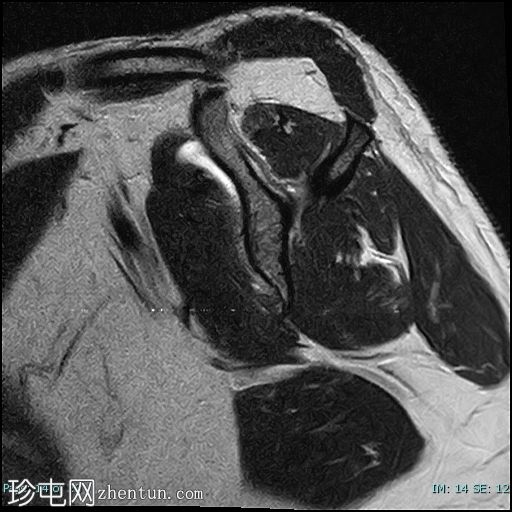

矢状位

T2

冈上肌腱前部纤维及肌腱止点-关键区交界处全层撕裂。撕裂间隙被T2/PD高信号液体填充。肌腱回缩2.1厘米,位于肩峰水平。

肱二头肌长头肌腱位于肱二头肌沟内,位置正常,信号和大小正常,腱鞘积液。鉴别诊断:腱鞘炎。

冈下肌和三角肌脂肪变性1级(Goutallier分级)。

肩肱关节软骨变薄,提示退行性肩肱关节软骨软化症。

肩峰下滑囊炎、三角肌下滑囊炎、喙突下滑囊炎和肩胛下滑囊炎。

本病例展示了退行性冈上肌腱撕裂的典型位置,即肌腱足印和关键区交界处。这与创伤性撕裂(通常发生在肌腱交界处)形成对比。